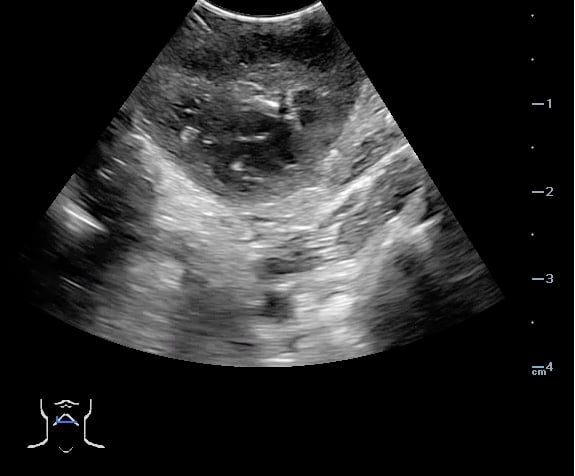

- Peritonsillar abscess is visualized as a hypoechoic or complex cystic structure

- Figure 45. and 46. PTA aspiration

- The depth of the abscess cavity from the mucosal surface should be noted to determine the length of the needle required to drain the abscess.

- The carotid artery is seen as an anechoic tubular structure along the posterolateral aspect of the tonsil on ultrasound. Its relationship to the abscess cavity should be determined. Color Doppler can help locate the carotid artery.

- Figure 47 and 48. PTA with color Doppler of carotid artery